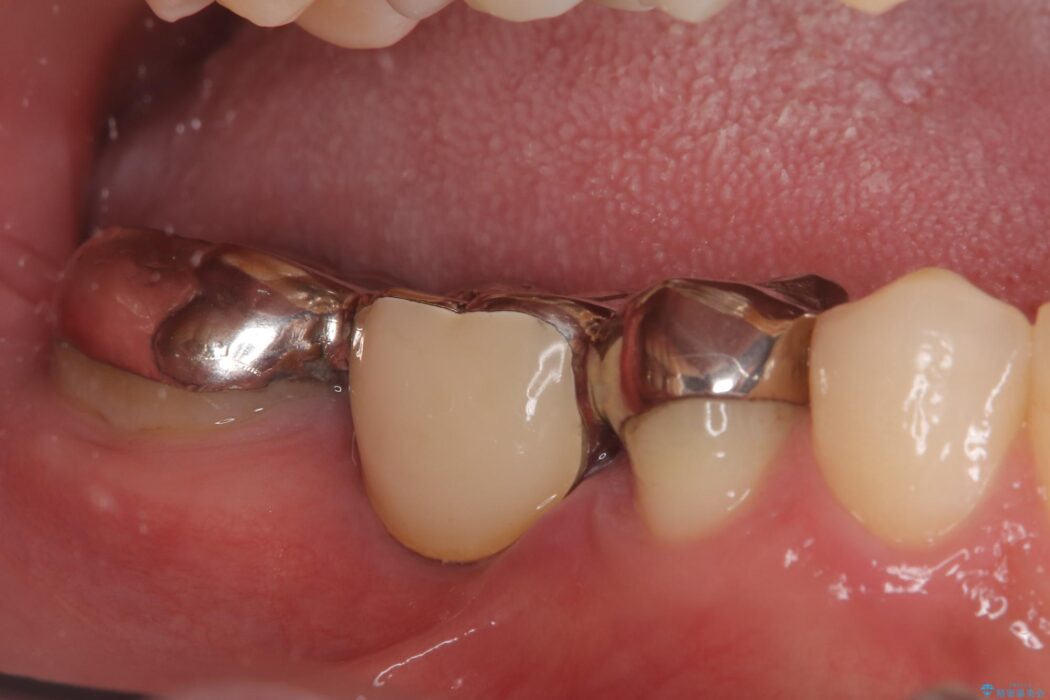

右下奥歯の5・6・7番に装着されていたブリッジの不具合を主訴にご来院された患者様です。

ブリッジは汚れが溜まりやすく、土台となる歯への負担も大きいため、患者様の希望に合わせそれぞれの歯をインプラント治療で独立させる治療計画を立てました。

ブリッジを外し、欠損している6番にインプラントを埋入。土台となっていた5番と7番は、セラミッククラウンで修復。